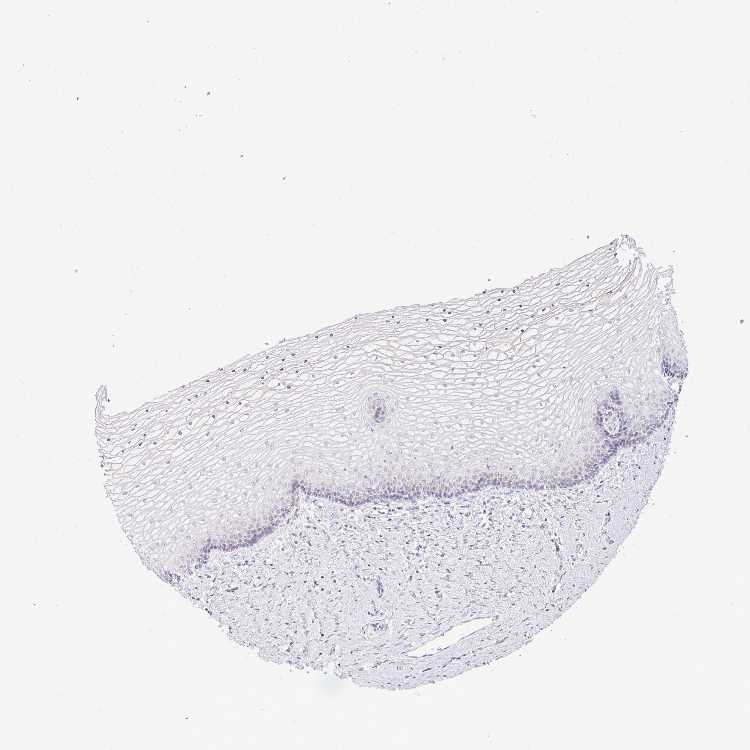

TISSUE PRIMARY DATA VAGINA Show tissue menu

VAGINA - Antibody stainingi

Antibody staining in the annotated cell types in the current human tissue is reported as not detected, low, medium, or high, based on conventional immunohistochemistry profiling in selected tissues. This score is based on the combination of the staining intensity and fraction of stained cells.

Each image is clickable and will lead to virtual microscopy that enables deeper exploration of all samples and also displays staining intensity scores, fraction scores and subcellular localization as well as patient and tissue information for each sample.

Antibody CAB017700

Squamous epithelial cells Low